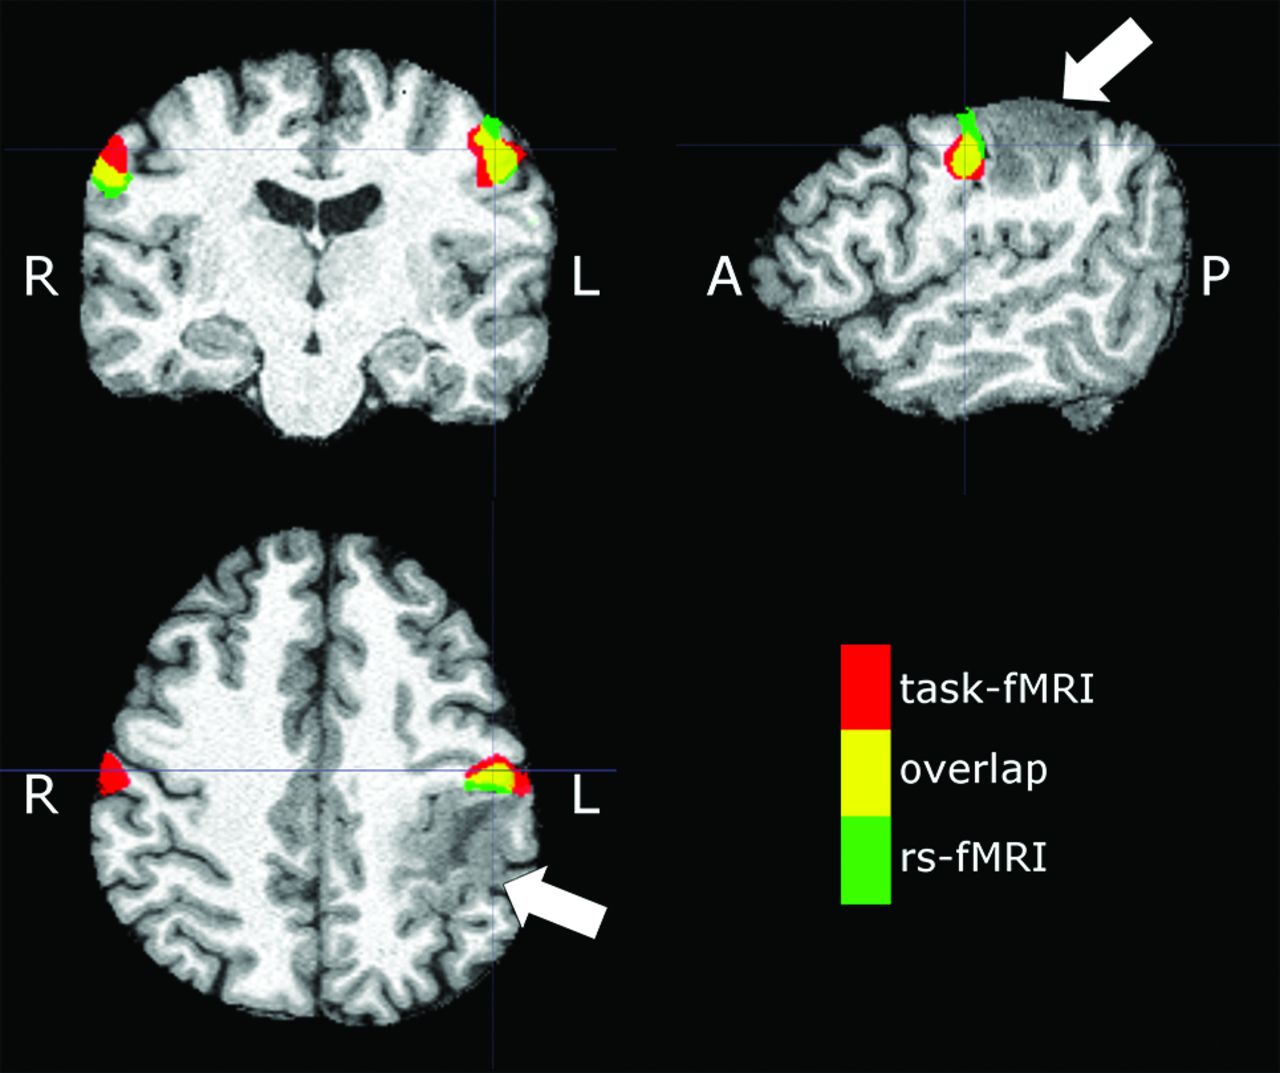

Our results show a strong concordance between the rs-fMRI and tb-fMRI in some of the subjects, demonstrating the potential utility of rs-fMRI as a viable preoperative mapping tool (Fig 7); however, there is significant variability across subjects. In particular, if rs-fMRI is to be used without a tb-fMRI acquisition, one must ensure that a reliability estimate of rs-fMRI can be calculated from the data itself. Improvement in technique and data analysis may overcome some of these limitations in the future. Increasing the scan time may improve the quality of rs-fMRI27 and thus potentially decrease such intersubject variability. Alternative methods of analysis such as seed-based analysis that have shown some promise in localizing the motor network in patients with brain tumors11,28 may also be considered. However, in the current study population of patients with brain tumors, accurate placement of seeds may be limited due to anatomic gyral distortion or compression. Therefore, an unbiased method such as ICA may be preferable. In addition, ICA remains an attractive choice due to availability of easy-to-use software such as the MELODIC tool in FSL (http://fsl.fmrib.ox.ac.uk/fsl/fslwiki/MELODIC) or the GIFT toolbox.

Sample subject (patient 23 in the On-line Table) demonstrating an expansile mass lesion centered in the postcentral gyrus (arrows). Signal abnormality is extended to the subcortical white matter of the precentral gyrus. Red denotes tongue motor task activation, green denotes the VSMN network identified from rs-fMRI (ICA 50), and yellow denotes areas of overlap between tb- and rs-fMRI.